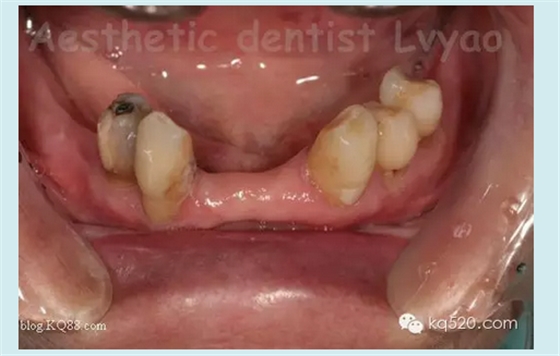

修復(fù)前口內(nèi)影像